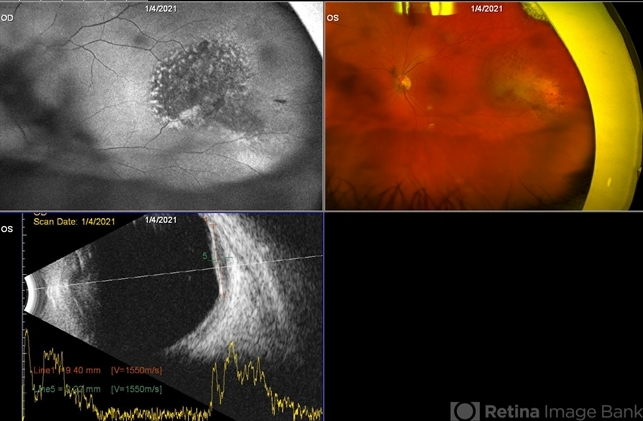

Optos California camera and Accutome 4 sight B scan ultrasonographer - Description

- Fundus photograph of the left eye in a 72-year-old patient diagnosed with Stage I pancreatic carcinoma involving the head of the pancreas diagnosed three months ago. The patient was seen for a routine diabetic retinopathy evaluation. Incidentally, this mass was observed in the temporal periphery of the left eye. Visual acuity 20/25 OU. OCT normal OU.